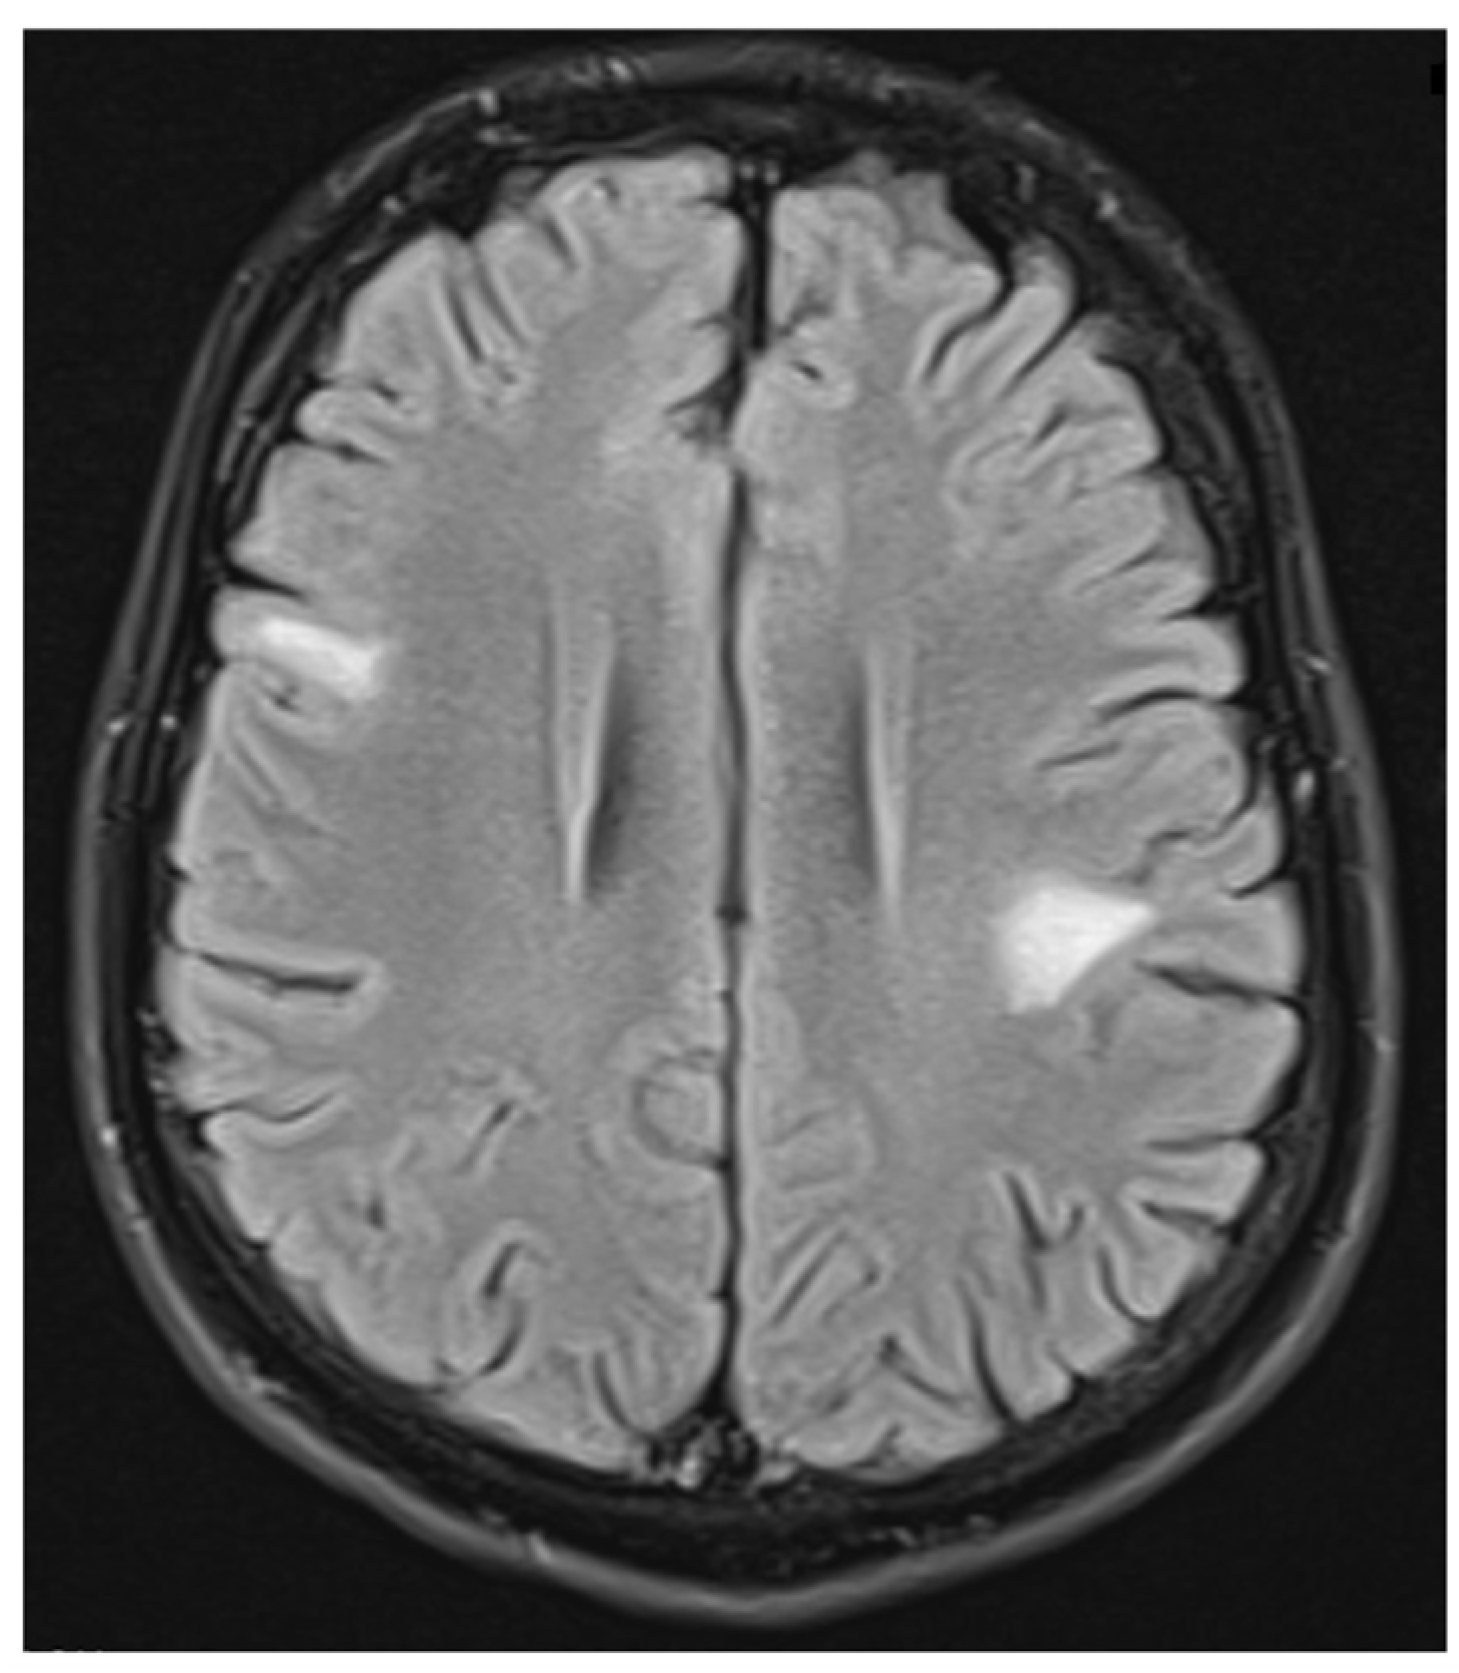

| Brain, brainstem or cerebellar syndrome | multiple ill-defined T2-hyperintense lesions in supratentorial and often infratentorial white matter, deep gray matter involvement, ill-defined T2-hyperintensity involving pons, middle cerebellar peduncle, or medulla, cortical lesion with /without lesional and overlying meningeal enhancement |